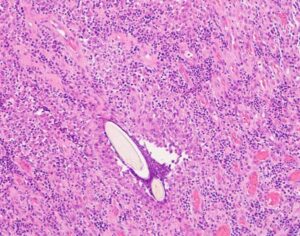

ワンちゃんが乳腺にできた複数のシコリを気にされて来院されました。bilateral mastectomyで対応しました。摘出後の病理組織検査の結果は、「R3-4間腫瘤:乳腺癌(複合型)」でそれ以外は「良性乳腺混合腫瘍」でした。無事元気に退院し、その後再発もなく経過は良好です。よかったね。